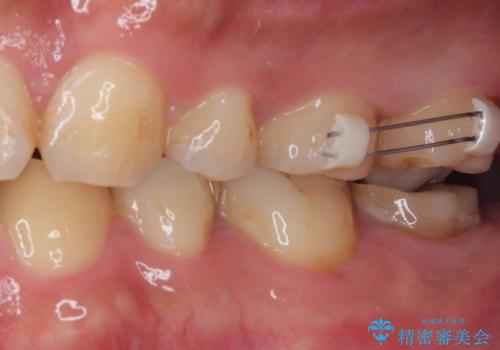

上顎の歯をアンカースクリューを用いた部分矯正により位置を修正し、根管治療後にPGAクラウンにて補綴治療を行うこととしました。

歯列が整ったことで咬み合わせが非常に安定しました。